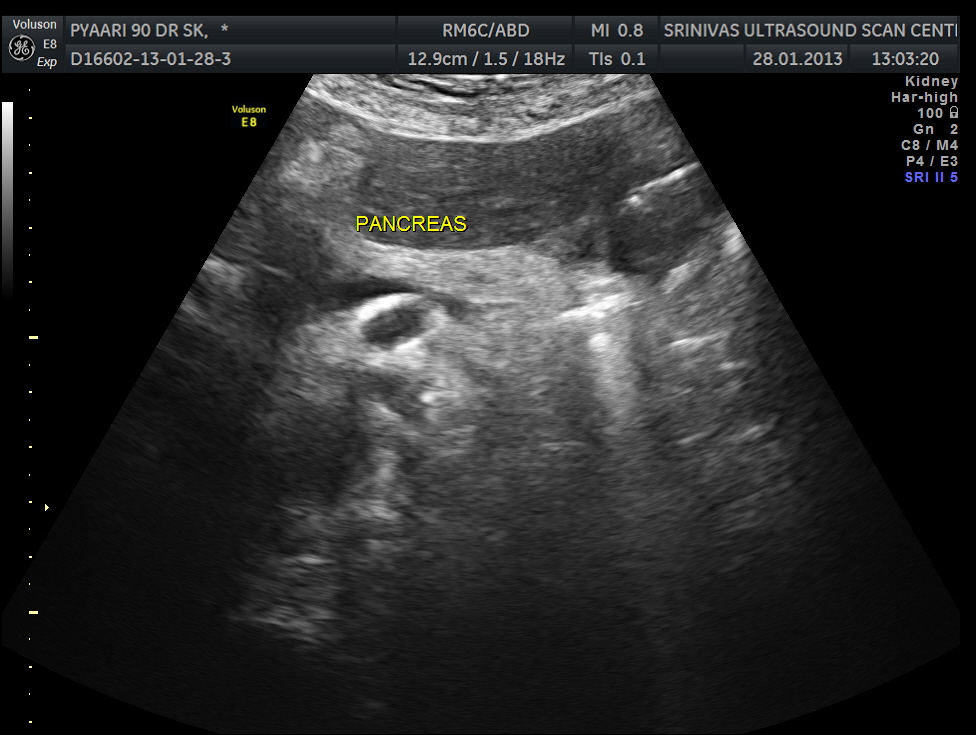

Pancreas appears normal.